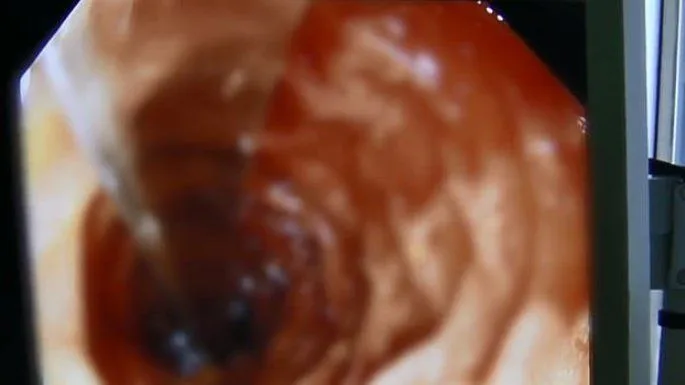

(ด้วยความที่ช้อนอยู่ในแนวนอน หมอจึงต้องจัดท่าทางให้มันอยู่ในแนวตั้งก่อน ถึงจะเอาออกมา Photo credit: Pear Video)

ดร. ซุน ถิงจี หมอผู้รับผิดชอบอาการของลิลลี่ เล่าถึงการผ่าตัดในครั้งนี้ว่า "จากภาพเอ็กซเรย์จะเห็นได้ว่า ช้อนติดอยู่ในลักษณะเป็นแนวนอน ฉะนั้นเราเลยต้องจัดมันให้เป็นแนวตั้ง แล้วค่อยเอาออกมา" แม้ช้อนที่เข้าไปติดอยู่จะทำให้เกิดการระคายเคืองและบวมในลำไส้เล็กของลิลลี่ แต่หมอและทีมผ่าตัดก็สามารถเอาช้อนออกมาได้สำเร็จ ก่อนจะให้พักฟื้นและอนุญาตให้กลับบ้านได้...